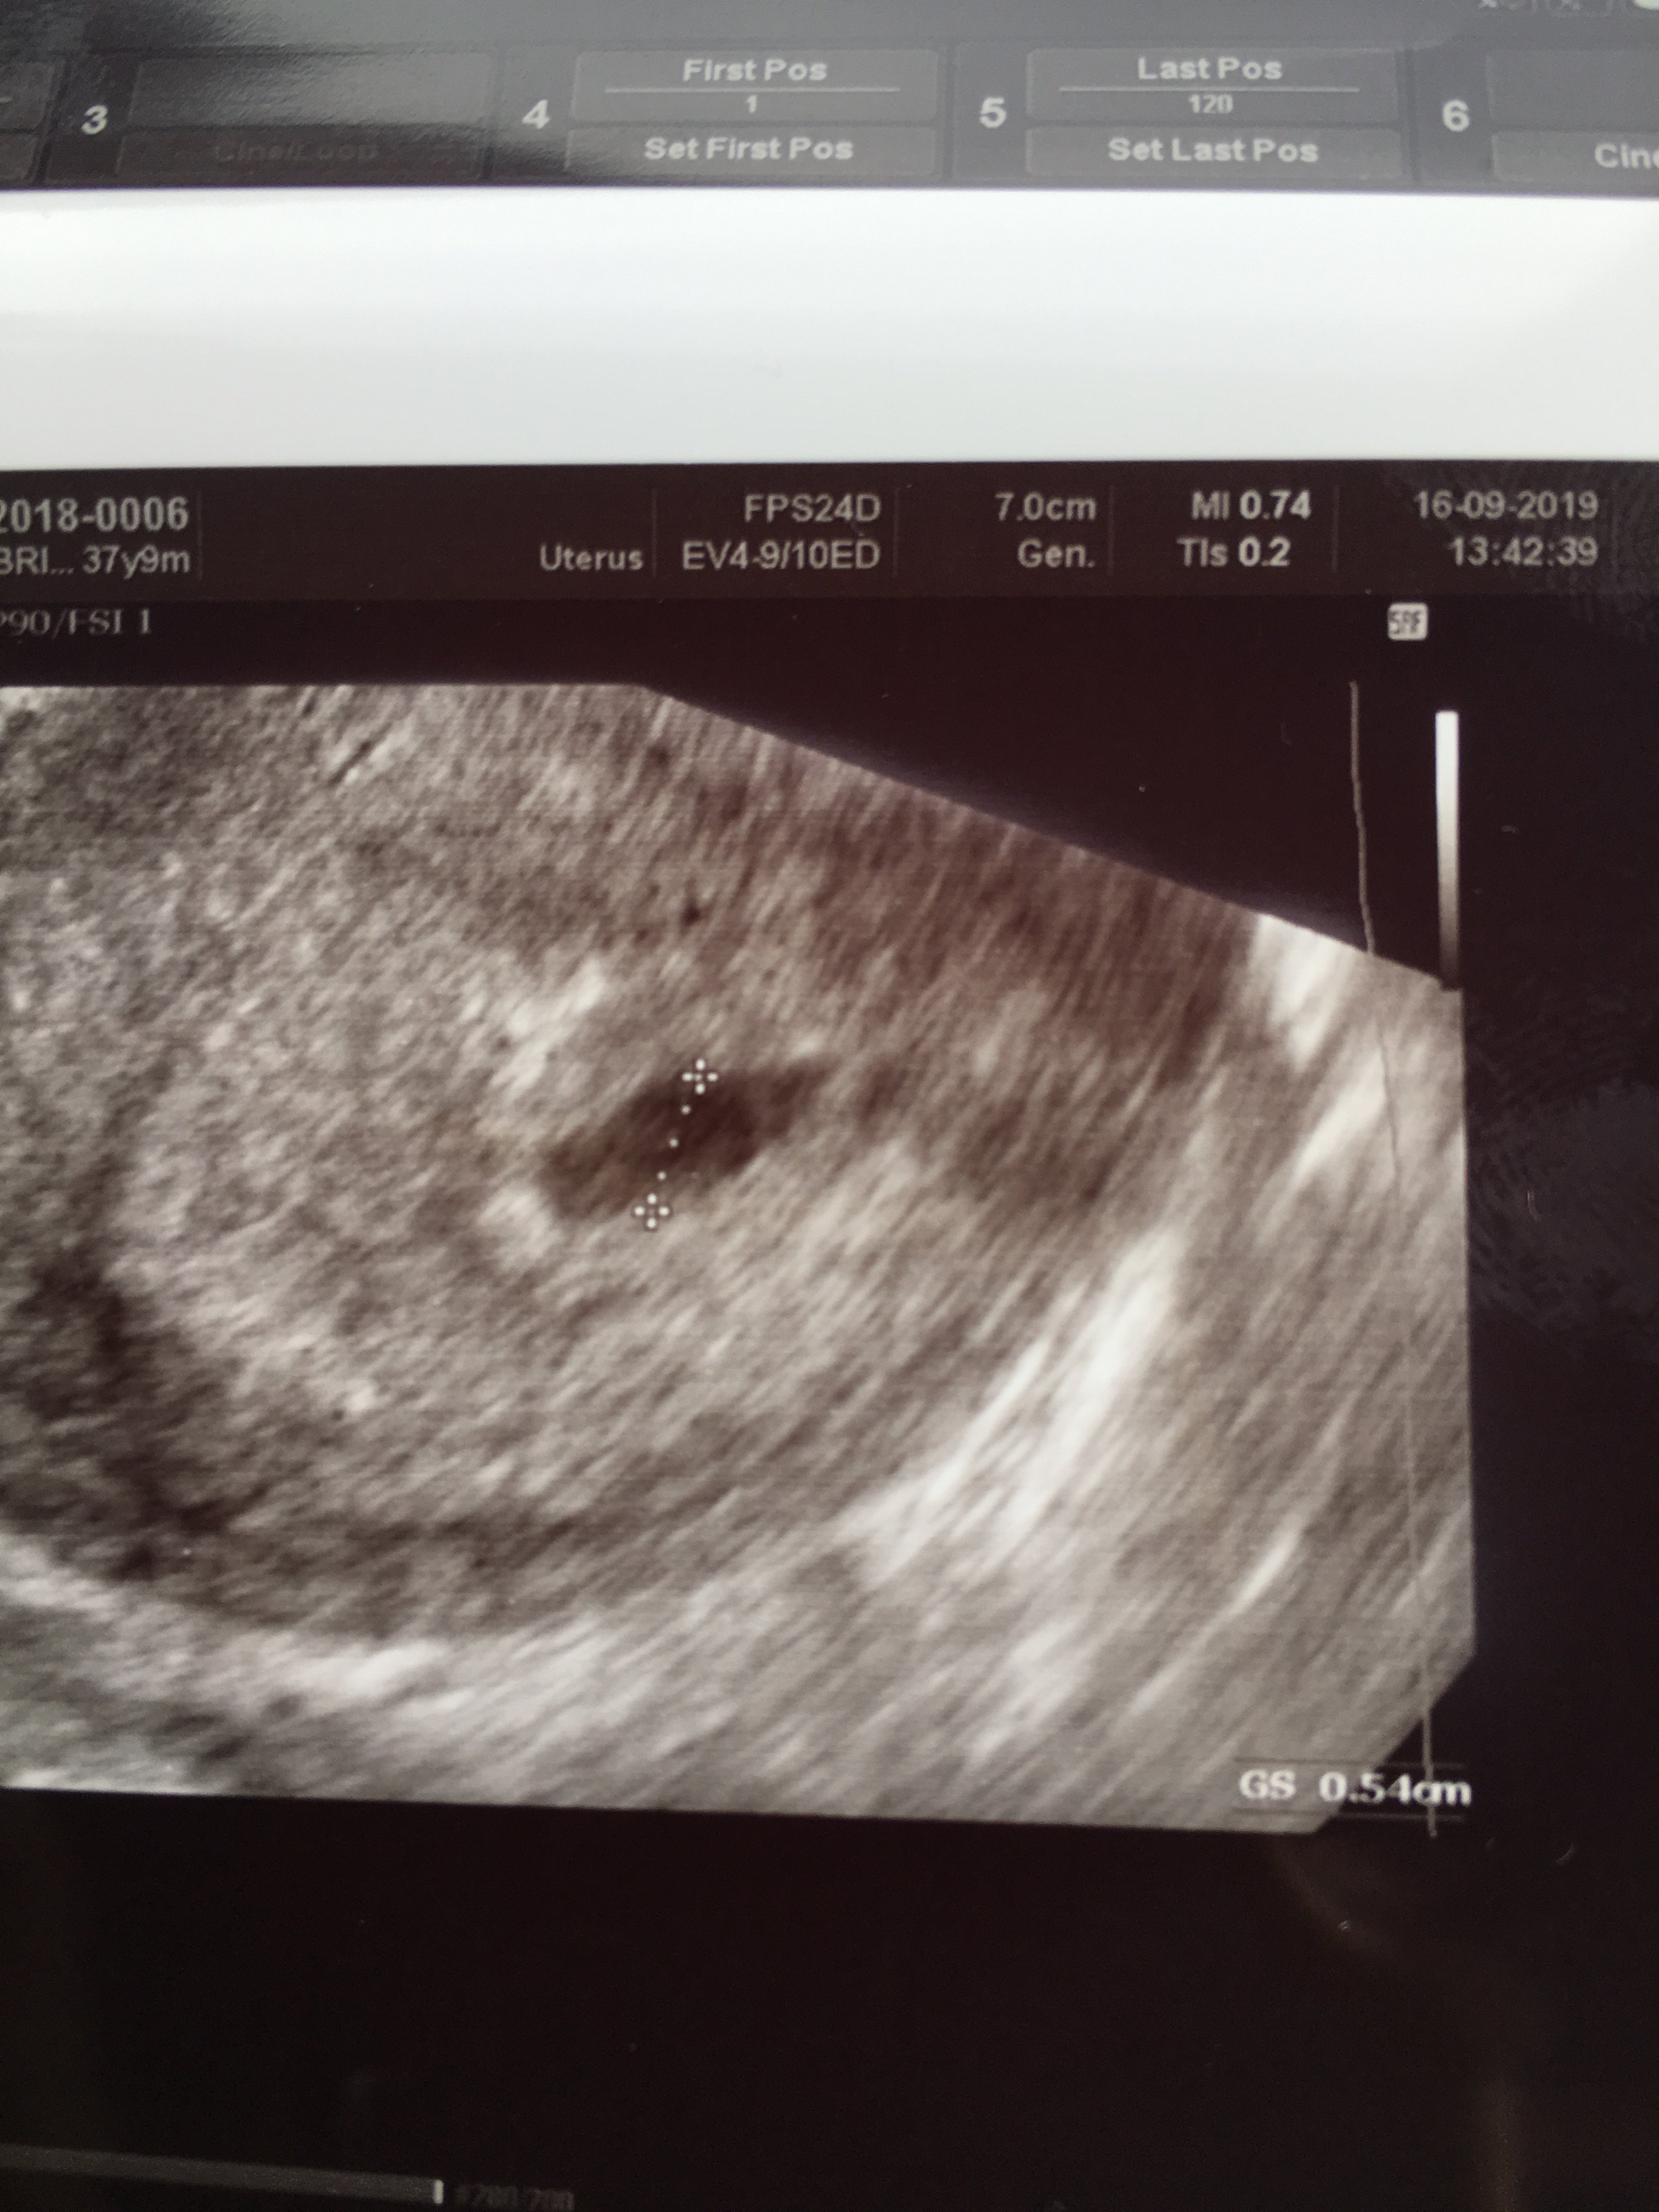

Zobacz załącznik 1023141Dziewczyny byłam u gina i poznajcie mojego kropeczka❤❤❤

Szczerze to byłam w takim szoku, ze niewiele się dowiedziałam. Ale najwazniejsze, ze jest:D:D i w dobrym miejscu, bo bałam się pozamacicznej.

Wciąż w to nie wierze, ale jestem bardzo szczęśliwa:D